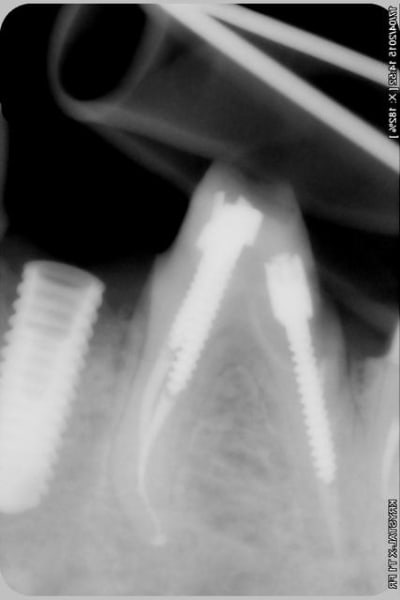

alors là pas du tout, le patient vient me voir pour des implants, donc je fais une étude du cas absence des molaires supérieures, couronnes mandibulaires très ancienne 45 racine cassée, 44 dévitalisée mais passablement déchaussée, donc avulsion de 45 et pose d'un implant avant de refaire les couronnes 46/47 et l'ensemble.

Échec implantaire, et oui ça arrive, même dans un cas paraissant simple.

Oui, un Px, le premier était un Reg.

l'os était tendre, ce qui explique le choix du Px

Pour les septiques, toujours certain que c'est du sur-traitement?